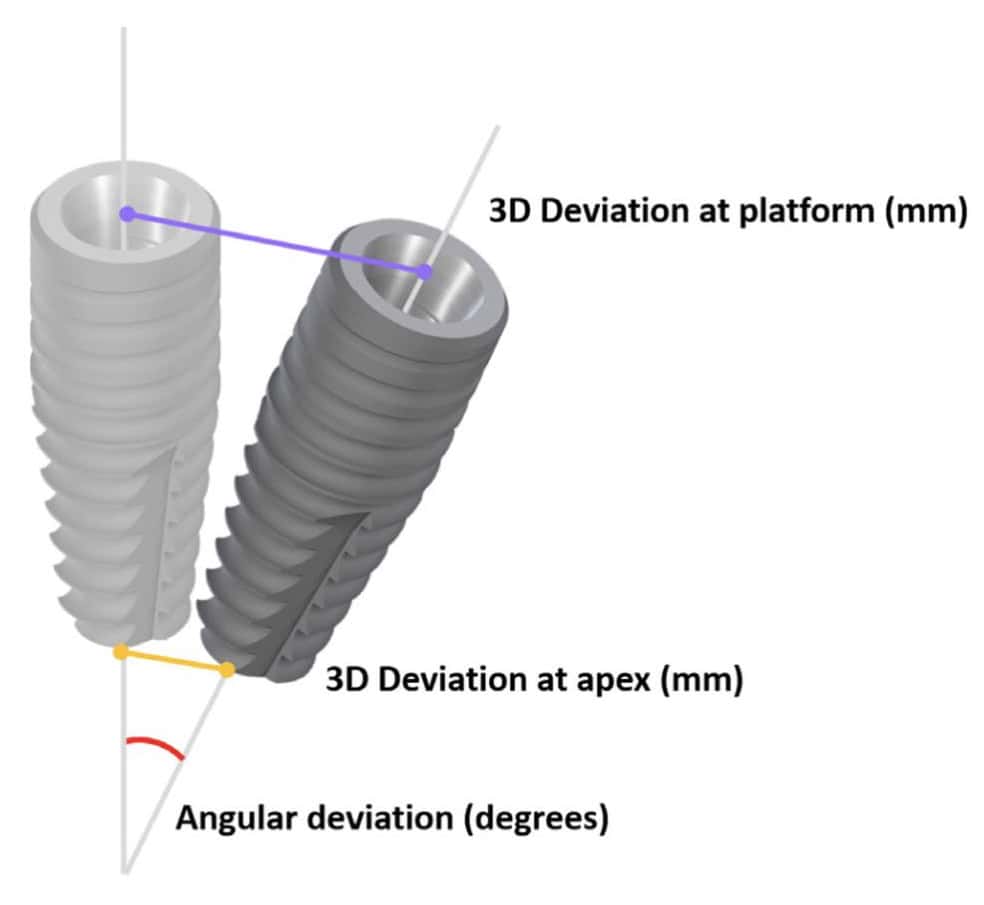

Accurate implant placement was the primary and most important advantage reported for CAIS. To measure the extent of this accuracy, researchers have used the 3-dimensional deviation from the planned position at the implant platform and apex and the deviation in the angle (Figure 1). Initial research pointed out to a significant increase in accuracy when CAIS was used, with the deviation reduced to roughly half of what it was in freehand implant placement for single implants. An earlier systematic review from the ITI Consensus Workshop of 2017, found that static CAIS would result to deviation of 1.2 mm at implant platform on average (1), suggesting that a safety margin of 2mm is to be considered when we use this technology. Although certainly a great development, is this something that could transform your practice? Many colleagues remained skeptical, especially those with long experience. After all, gadgets are always cool, but we’ve been placing implants with great success already. Is it worth all additional investment and effort?

Assessing implant placement accuracy

Typical parametres measured to assess accuracy of implant placement: 3D deviation at platform and apex and angular deviation.